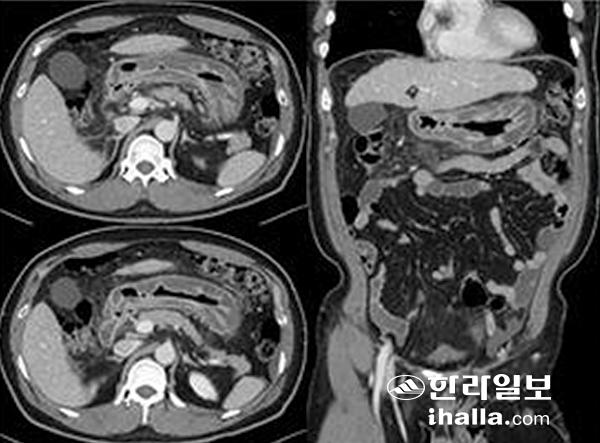

컴퓨터단층촬영상 고래회충증 소견. 전형적으로 위에 발생한 고래회충증이며, 환자는 통증 6시간 전에 생선회를 먹었고 위 전체의 부종 소견을 보인다. 사진=제주대학교병원

사진은 소장에 발생한 고래회중증의 영상 이미지. 환자는 통증 2일전 생선회를 먹었고, 원위부 소장의 협착과 근위부 소장이 확장돼 있어 장폐쇄 소견을 보인다. 사진=제주대학교병원